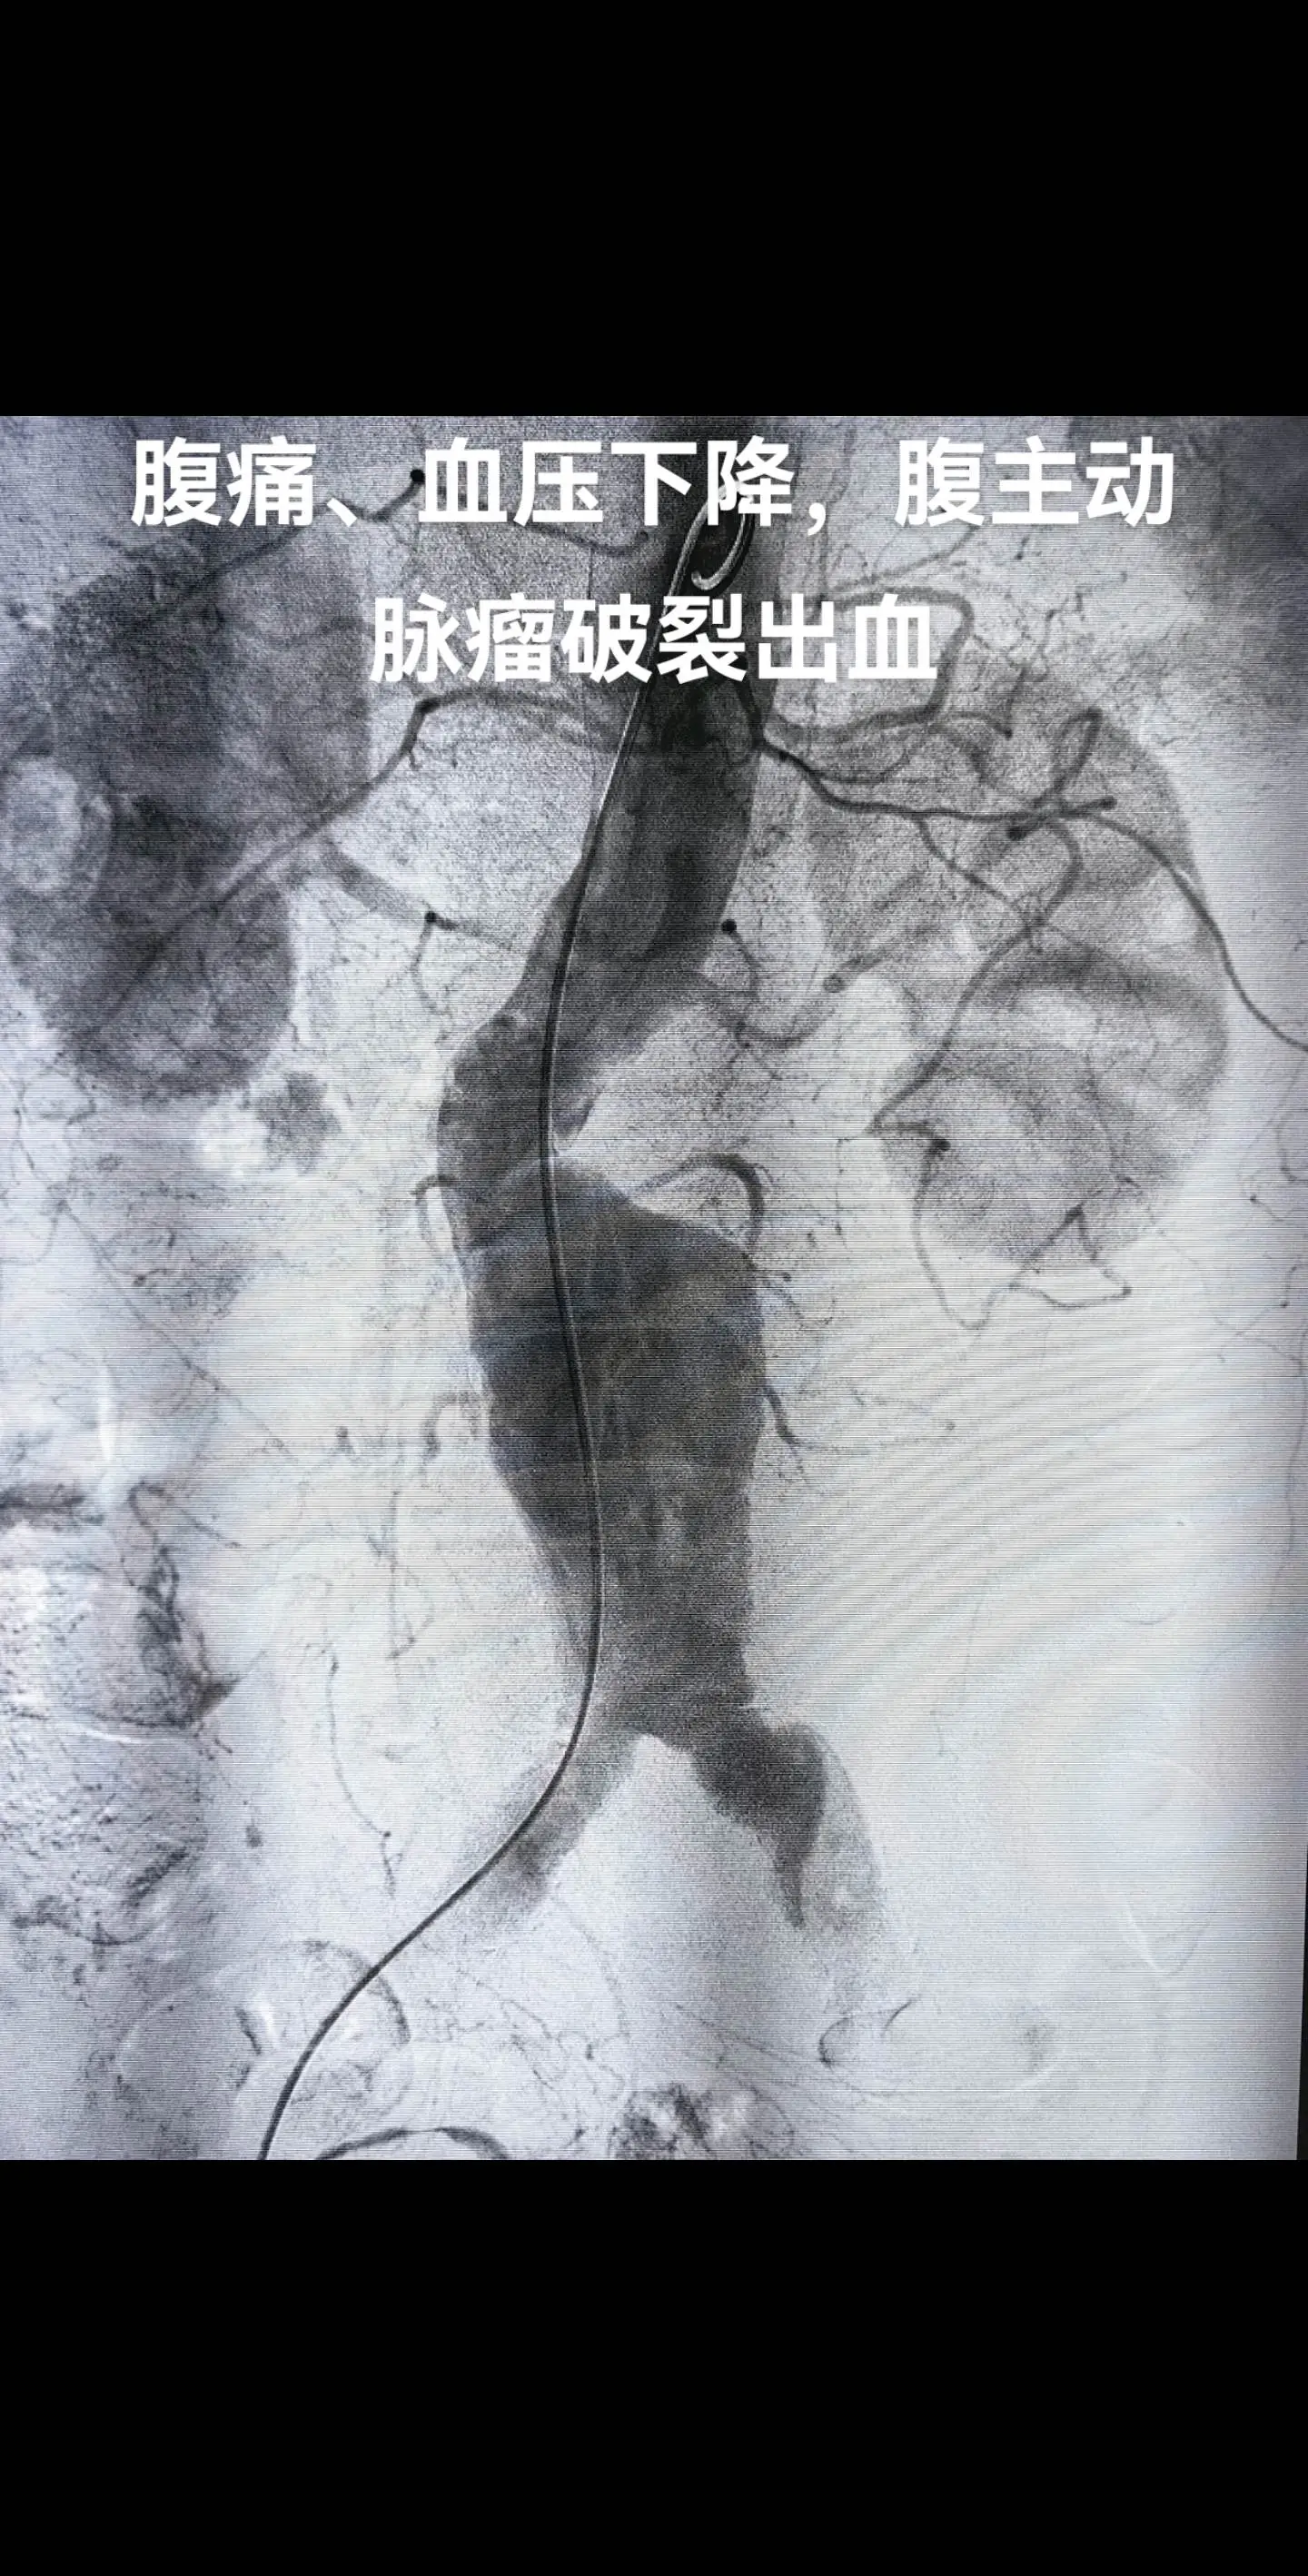

20年4厘米的腹动脉瘤长到了9厘米,此次腹痛、血压下降,动脉瘤破裂出血,紧急“拆弹”,动脉瘤瘦身成功腹主动脉瘤微创介入